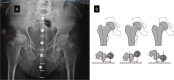

Preoperative planning is mandatory to achieve the restoration of a correct and personalized biomechanics of the hip.The radiographic review is the first and fundamental step in the planning. Limb or pelvis malpositioning during the review results in mislead planning.Correct templating is possible using three different methods: acetate templating on digital X-ray, digital 2D templating on digital X-ray and 3D digital templating on CT scan.Time efficiency, costs, reproducibility and accuracy must be considered when comparing different templating methods. Based on these parameters, acetate templating should not be abandoned; digital templating allows a permanent record of planning and can be electronically viewed by different members of surgical team; 3D templating is intrinsically more accurate. There is no evidence in the few recently published studies that 3D templating impacts positively on clinical outcomes except in difficult cases.The transverse acetabular ligament (TAL) is a reliable intraoperative soft tissue reference to set cup position.Spine-hip relations in osteoarthritic patients undergoing hip joint replacement must be considered. Cite this article: EFORT Open Rev 2019;4:626-632. DOI: 10.1302/2058-5241.4.180075.